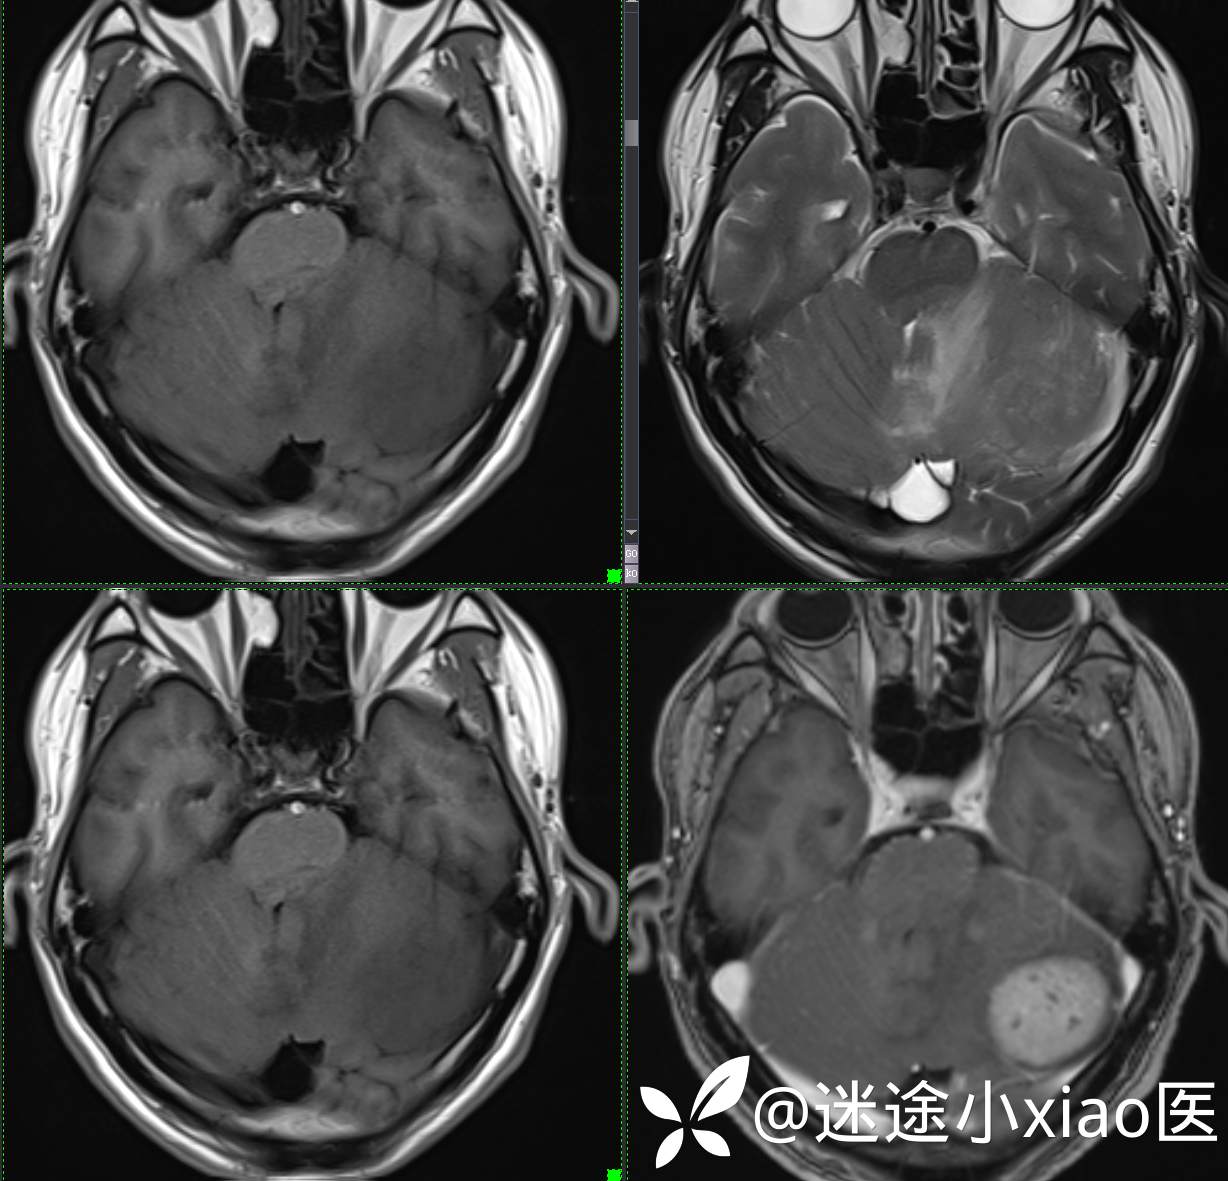

头颈组15:男,62岁,左侧小脑半球占位,原发?转移?是否有意外?

主 诉: 头晕、恶心呕吐半月余。

现病史: 患者半月前无明显诱因下明显头晕,伴恶心呕吐,无意识丧失、无智力明显下降,无视物模糊,无耳鼻腔出血,无四肢抽搐、畸形,无胸闷气促、呼吸困难。

既往:膀胱癌手术史。